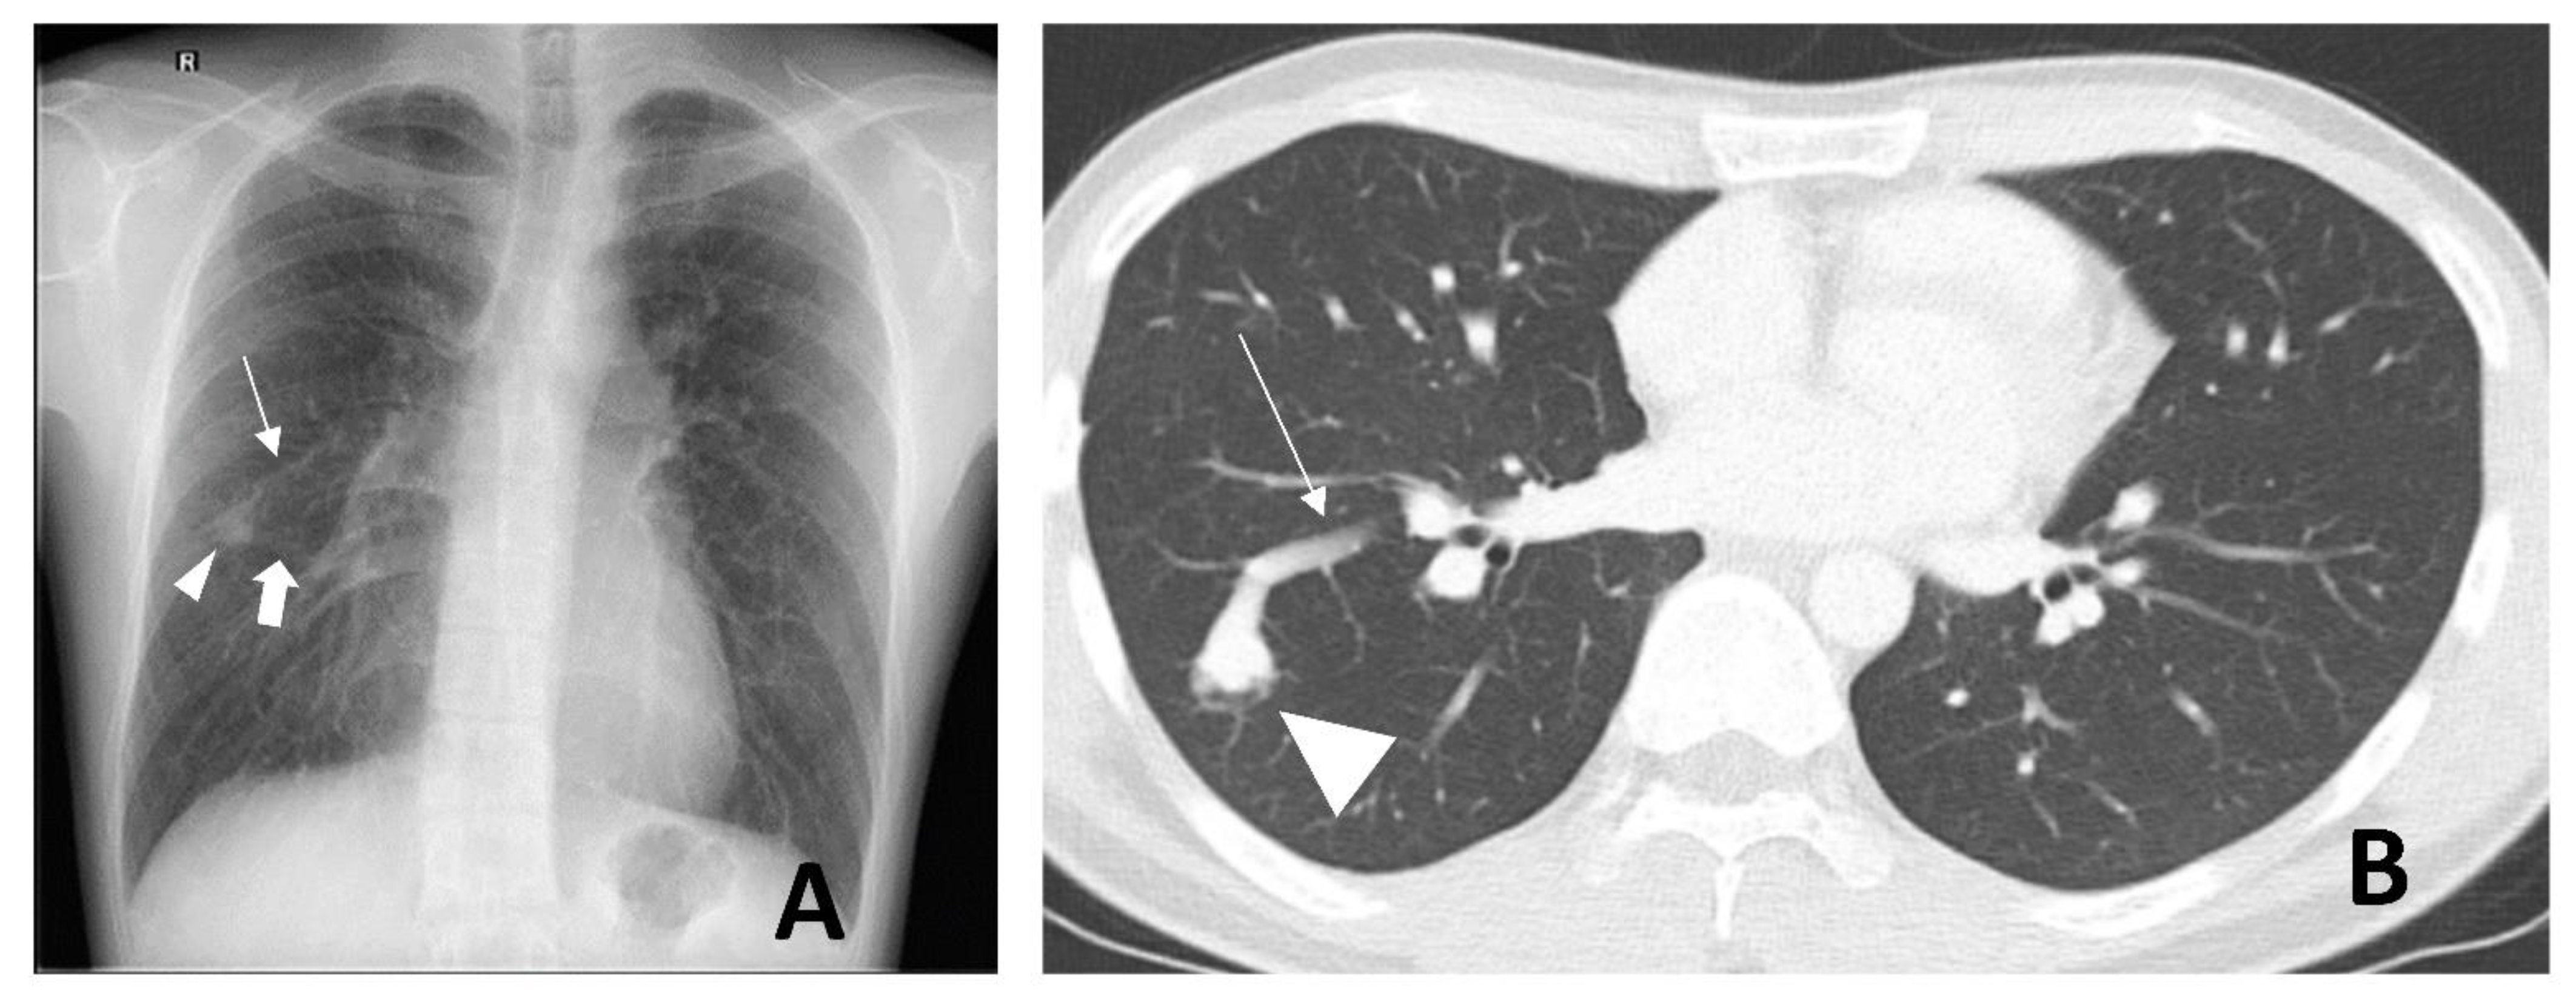

2. Radiological Diagnosis